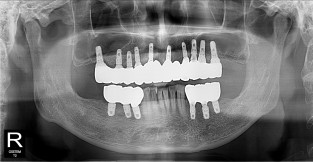

• 3

전체어금니

치료기간 : 2021-10-20 ~ 2023-08-31

1. 상기 x-ray 이미지 모두 동일한 해당 의료기관에서 진료한 환자입니다.

2. 상기 x-ray 이미지 모두 동일 인물의 것입니다.

3. 치료 전 이미지는 2021-10-20에 촬영했으며, 치료 후 이미지는 2023-08-31에 촬영하였습니다.

4. 상기 x-ray 이미지 모두 동일 조건에서 환자분의 동의를 받아촬영되었습니다.

* 임플란트 시술은 환자분의 상태(고혈압, 당뇨 등)에 따라 부작용이 있을 수 있으니, 반드시 전문의와 상담이 필요합니다.

* 임플란트 수술 부작용

: 수술 후 출혈, 교합, 통증, 붓기, 염증 등의 문제점이 발생할 수 있습니다.)